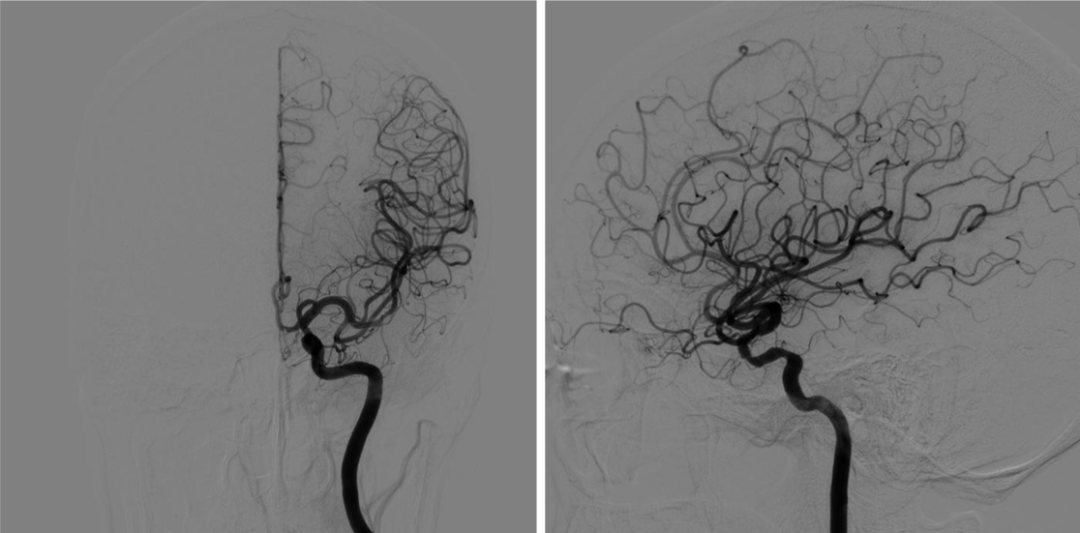

颈总动脉造影

右侧颈内动脉超选造影

左侧颈内动脉超选造影